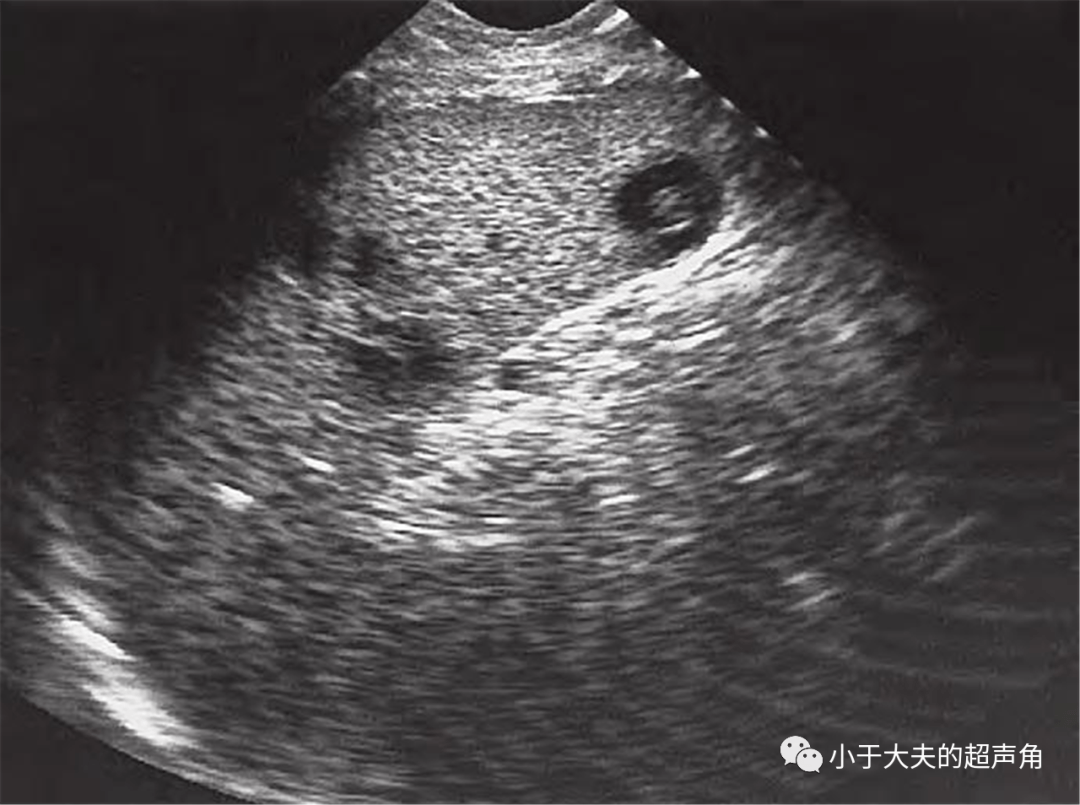

超声随响第27期肝念珠菌病candidiasis

图片尺寸1080x805